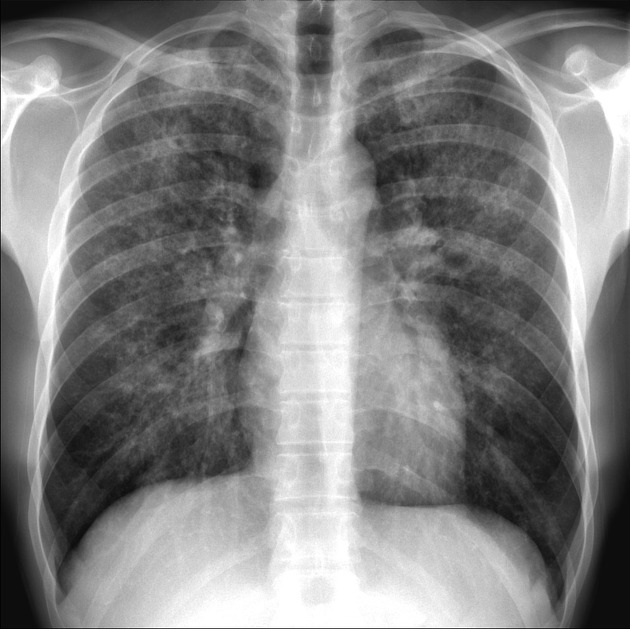

82 yo F with fatigue and AMS? Your interpretation?

What is bilateral pulmonary infiltrates with more confluent opacity in the right lung, consistent w/ multilobar pneumonia?